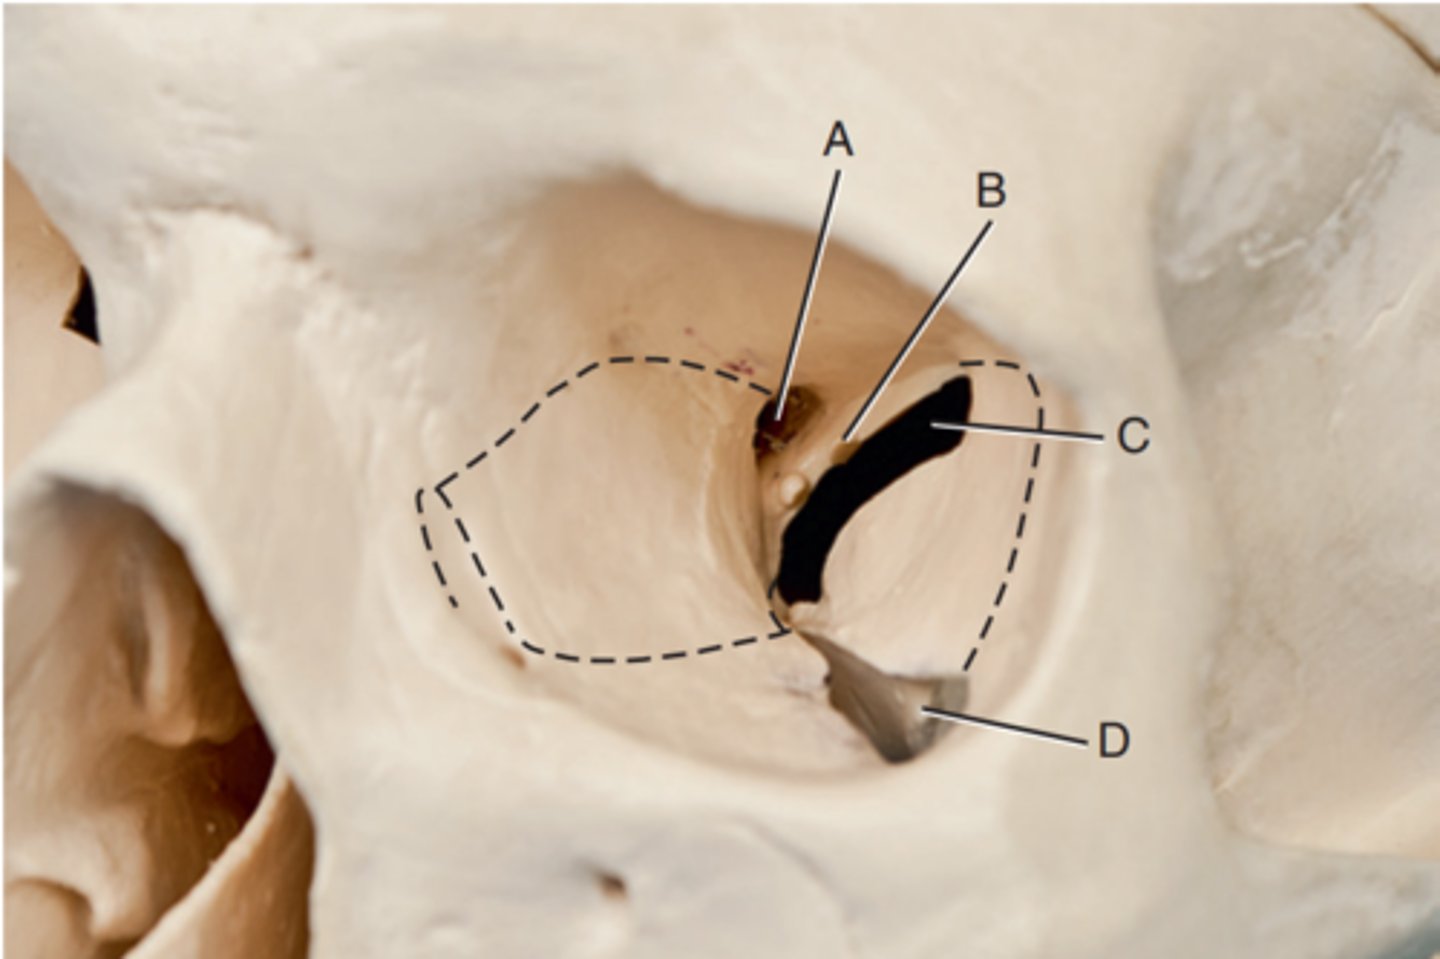

Optic foramen

Label A

Sphenoid strut

Label B

Superior orbital fissure

Label C

Inferior orbital fissure

Label D

Orbital plate of frontal bone

Label A

Sphenoid bone

Label B

Optic foramen and canal

Label C

Superior orbital fissure

Label D

Infraorbital margin (IOM)

Label E

Sphenoid strut

Label F

Lateral orbital margin

Label G

Supraorbital margin

Label H